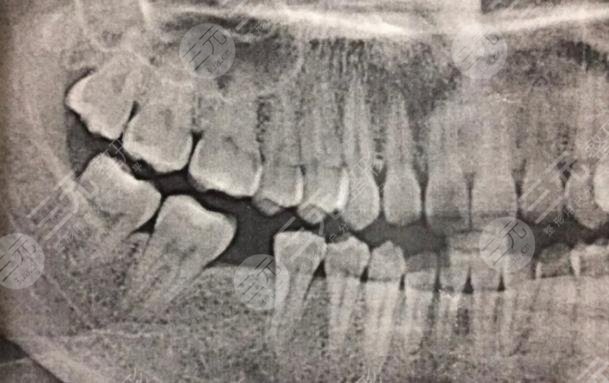

我的牙齒有一顆牙齒壞了很久了,所以我一直想要修復(fù),但是我又不想拔掉,所以就很糾結(jié),不知道怎么樣的方式才能夠改良,經(jīng)過朋友的一番介紹說,我還是選擇到口腔醫(yī)院里面檢查一番,然后再決定具體的緩解方法。在和口腔醫(yī)院的醫(yī)生溝通之后,他說像我這種方情況必須要把原有的壞牙拔掉之后換新的牙齒,不會有口腔造成疾病的情況。